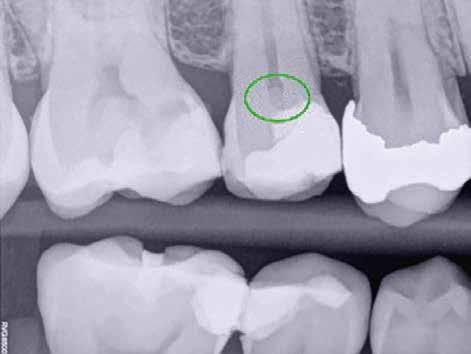

Egy 38 éves nőbeteg a korábban kezelt jobb felső második kisőrlőfogából (1.5) kiinduló mérsékelt fájdalom miatt jelentkezett rendelésünkön. A kórtörténetében jelen panasza szempontjából releváns információ nem szerepelt. A beteg a klinikai vizsgálat során vertikális kopogtatásra enyhe érzékenységet jelzett. A kérdéses fog körül mérhető szondázási mélység és a fogmobilitás fiziológiás volt. Periapicalis röntgenfelvételen egy, a fog gyökércsúcsán túl presszálódott betört gyökérkezelő műszerből származó eszközfragmentumot láttunk (2. a. ábra). A preoperatív CBCT-felvétel a buccalis csontlemez épségét igazolta (2. b-c. ábra). A fog revíziója öt hónappal korábban történt. A már előzőleg gyökérkezelt, gyökértömött, majd revideált 1.5-ös fog esetében a diagnózisunk periodontitis periapicalis symptomatica volt. A periapikális elváltozás kezelése érdekében navigált endodonciai mikrosebészeti beavatkozást végeztünk.

a-m. ábrák: Preoperatív röntgenfelvétel (a) és preoperatív CBCT-felvétel a jobb felső 5-ös (1.5) fogról, sagittalis (b) és axialis (c) nézetek. Az intraorális szkennelés során kapott STL-fájl (d). A 1.5-ös fog navigált endodonciai mikrosebészeti beavatkozásához tervezett sablon (e). A 1.5-ös fog navigált endodonciai mikrosebészeti beavatkozásához nyomtatott sablon (f). Teljes vastagságú mucoperiostealis lebenyt emeltünk (g). A sablont a helyére illesztettük, és a csontablak határait jelöltük (h). A fog gyökerén kívül eső, betört eszköz a 1.5-ös fog periapicalis régiójában (i). Az eltávolított betört eszköz (j). A rezekció, retrográd preparáció és a TotalFill BC RRM Fast Set Putty anyaggal elkészített retrográd gyökértömés utáni röntgenfelvétel (k). A lebenyt varratokkal rögzítettük (l). A kétéves kontroll során készített röntgenfelvétel (m).

gítségével tovább módosítottuk. Az így kapott sebészi sablon egyértelműen meghatározta a periapikális terület eléréséhez szükséges csontablak határait (2. e-f. ábra) Helyi érzéstelenítést követően teljes vastagságú mucoperiostealis lebenyt képeztünk, majd a buccalis csont feltárását követően (2. g. ábra) a sablon segítségével bejelöltük a preparálandó csontablak határait (2. h. ábra). A csontablak kialakítása során Piezotome CUBE LED kézi-darabot alkalmaztunk, majd a leemelését követően a betört eszközt megkerestük (2. i. ábra) és eltávolítottuk (2. j. ábra). A rezekciót ultrahangos megmunkáló fejekkel (ACTEON) végeztük, majd retrográd preparáció következett.

A retrográd gyökértömés elkészítése során TotalFill BC RRM Fast Set Putty-t (FKG) használtunk (2. k. ábra). A lebeny széleit 5/0-s Prolene varratokkal egyesítettük (2. l. ábra). A varratok a műtétet követően 72 órával kerültek eltávolításra. A beteg két évvel később kontrollröntgen készítése céljából érkezett rendelőnkbe. A vizsgálat során a fog tünetmentesnek és funkcióképesnek bizonyult (2. m. ábra).